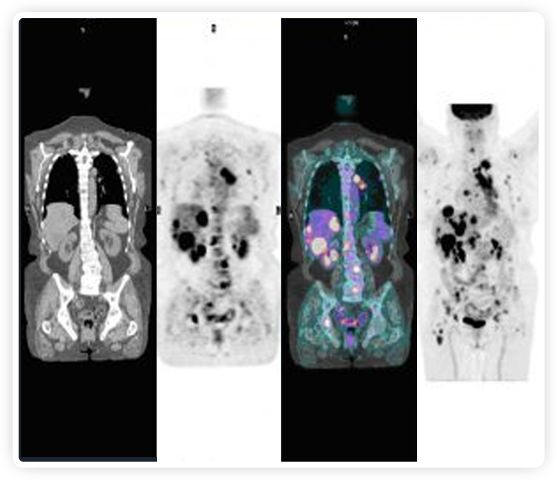

PET+放療共同治療

RefleXion將PET成像與立體定向放射治療相結(jié)合。在注射示蹤劑后,RefleXion的技術(shù)基于示蹤劑信號實時地在一個或多個目標(biāo)上引導(dǎo)治療性X射線。使用這種專有方法,RefleXion的平臺有可能比現(xiàn)有系統(tǒng)向癌癥病變提供更高劑量的輻射,并改善周圍健康組織的保護(hù)。

為了避免PET長圖像采集時間,RefleXion開發(fā)了一項專利技術(shù)使用重合的PET光子對來指導(dǎo)放射治療束,因為實時檢測發(fā)射的光子,為生物指導(dǎo)提供了一種時間有效的方法。